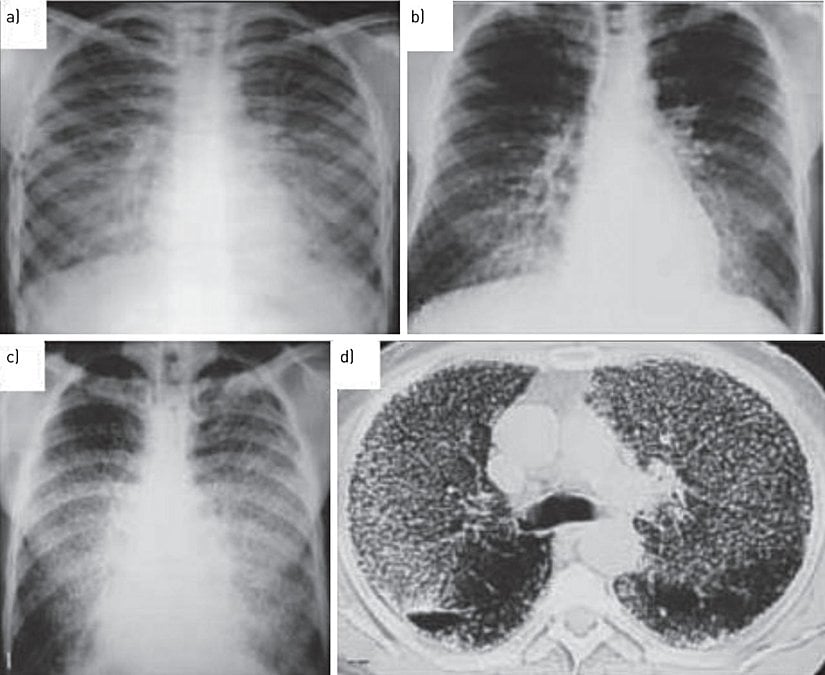

- Akciğer dokusunda görülen semptomlar; diffüz, bilateral, simetrik mikronodüler kalsifikasyonlardır. Göğüs filmi çekildikten sonra akciğerlerde görülen nodüller "kum fırtınası" olarak tanımlanmaktadır.[7], [10]

Tanı için yüksek rezolüsyonlu bilgisayarlı tomografinin oldukça elzem bir yeri olduğu ifade edilebilir. Kesin tanı koyulması için akciğer biyopsisi şarttır. Akciğerlerdeki nodüllerin iki taraflı alt zonlarda yaygın biçimde kendisini göstermesi hastalığın teşhisi için bir diğer karakteristiktir. Her yaşta görülebilen bu hastalıkta, en sık tanı konulan yaş aralığının 30-50 arasında olduğu bilinmektedir. Hastanın durumuna göre SFT ve karbonmonoksit difüzyon testi yapılması gerekebilir.

Teknesyum-99 difosfonat kemik sintigrafisinde difüz pulmoner tutulumun saptanması da teşhis için önemlidir. Yüksek rezolüsyonlu bilgisayarlı tomografide tanı için belirleyici olarak akciğer bölgesinde görülen fonksiyonel ve fizyolojik olarak bozulmalar, parankimal bantlar, subplevral interrstisyel kalınlaşma, buzlu cam opasiteleri, paraseptal amfizem, interlobüler septal kalınlaşma, sentrlobüler amfizem, bronşektazi, peribronkovasküler interstisyel kalınlaşma, panasiner amfizem ve plevral kalsifikasyon tespit edilebilir.[3], [4], [6], [8], [11]